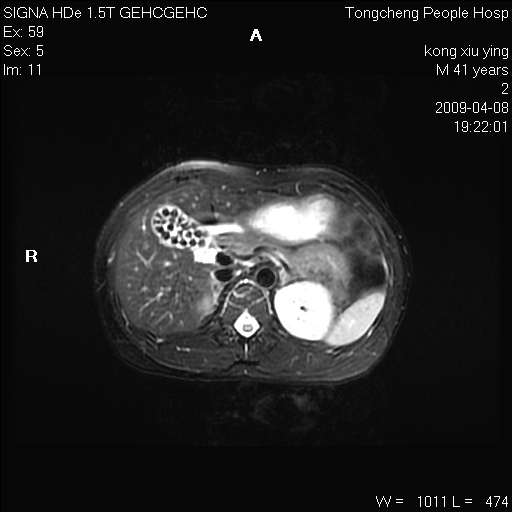

标题: CL1008:【经典】胆囊石榴籽样结石。 [打印本页]

标题: CL1008:【经典】胆囊石榴籽样结石。

女,41岁。健康体检——彩超提示:胆囊显示不清。平素健康,无不适感。

腹部mr扫描及mrcp,图像如下: